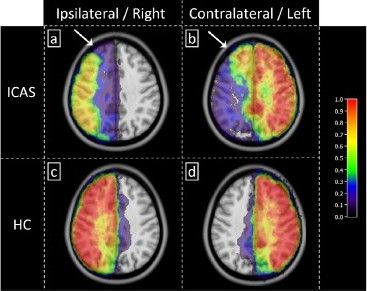

onlinelibrary.wiley.com/doi/full/10....

#neuroimaging #neurology #neuroskyence #radiology #mrspectroscopy #3tesla #myoinositol #glycine

Free read

onlinelibrary.wiley.com/doi/full/10....

#neuroimaging #neurology #neuroskyence #radiology #mrspectroscopy #3tesla #myoinositol #glycine

Free read